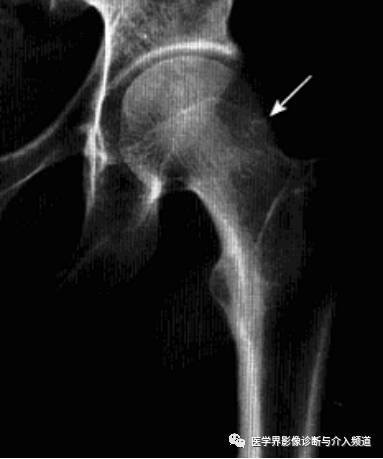

髋关节撞击综合征

也称股骨髋臼撞击综合征,是由于股骨近端和髋臼盂缘间解剖的异常,或解剖正常但长期不正常外力作用于髋关节,导致两者长期不正常接触、碰撞,产生反复的微型创伤致使关节盂缘和关节软骨退变,从而引起慢性髋关节疼痛及髋关节屈曲和内收受限的疾病。分为凸轮撞击和钳夹撞击两个类型。

病理:股骨头软骨呈明显退变现象,关节唇骨化、瘢痕化、体积增大、软骨下撕裂。

临床表现:凸轮撞击多见于喜欢运动的青年男性,钳夹撞击多见于活动较多的女性。典型表现为腹股沟区疼痛,通常在活动或久坐后加剧,呈间歇性,后期呈持续性。病变常呈单侧性,查体时髋关节活动受限,撞击试验阳性。

影像诊断:X线平片是基本检查方法,直立骨盆正位及髋关节侧位片。

平片:①凸轮撞击型,正位片示头颈连接处扁平,呈“左轮枪柄”样畸形,侧位片示股骨头颈凹陷减少,中心边缘角变小<16度,②钳夹撞击型,髋臼窝过深,髋臼后倾,呈相交8字征,偏心距缩短<9mm。

CT:三维CT可测量股骨头颈连接处前外侧偏移量减低,股骨头颈联合处前上缘可见骨性突起。

MRI:股骨头颈凹陷减少(α>50°),股骨颈宽度与股骨头半径比率增大,髋臼后倾。盂缘退行性改变,撕裂、囊肿,关节间隙后期出现狭窄,周围肌肉炎症。